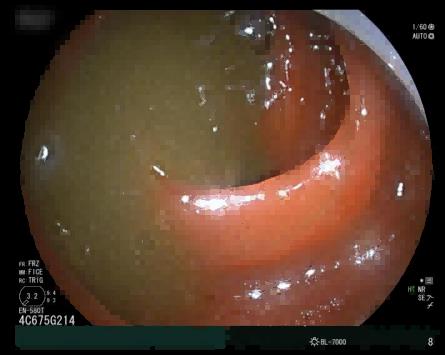

在麻醉团队的配合下,进展顺利。小肠镜入肛后,在距回盲瓣约70厘米处,发现了“罪魁祸首”——一枚直径约为10厘米的巨大粪石,相当于成年人拳头大小。郭勤果断操作,上演“碎石术”,使用圈套器将粪石逐步分解粉碎后,再用网篮带出碎石,如此往复。她始终小心翼翼,手法轻柔,以免误伤肠壁。